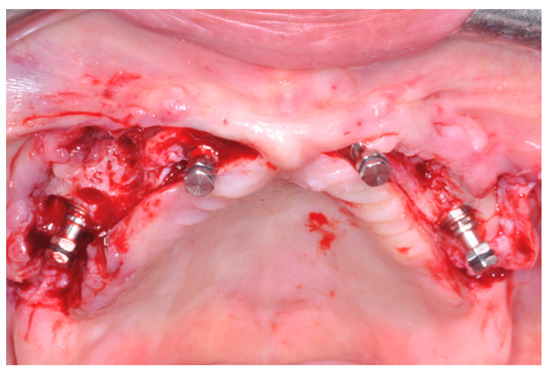

Six months after the surgery, patients were recalled for maintenance therapy and occlusion was checked when screw-retained prostheses were removed to be cleaned (Figure 2). Subsequent maintenance follow-ups depended on the patient’s degree of hygiene, verified in the sixth month.

In case of framework fracture, or to prevent them, the original metal-resin prostheses were gradually replaced by newly made screw-retained monobloc white resin (top.lign professional, Bredent, Senden, Germany) prostheses using a reinforced titanium framework, characterized externally by layers of enamel resin of various shades of pink and white colors (monolithic resin metal reinforced prostheses; Figure 3).